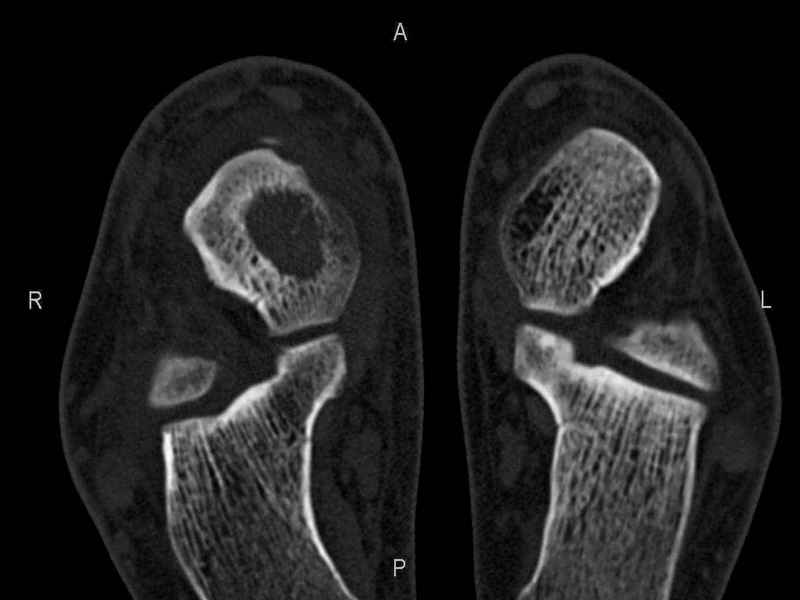

[Ortho] Рассекающий остеходрит + киста шейки тарана

Уважаемые коллеги, обратился за помощью пациент, мужчина, 25 лет. С жалобами на болевой

синдром в области голеностопного сустава и среднем отделе стопы. Травму отрицает. Со слов,

болевой синдром в течении 1 года. Последние 1-1.5 мес периодически вынужден пользоваться

костылями. После ограничения нагрузки боли уменьшаются. Соматически здоров. До появления

болей активно занимался рукопашным боем.

На СКТ картина рассекающего остеохондрита блока

таранной кости, киста шейки таранной кости с признаками импрессии суставной поверхности. А

также - разрастания переднего края б\берцовой кости сопровождающиеся клиникой импиджмент

синдрома.